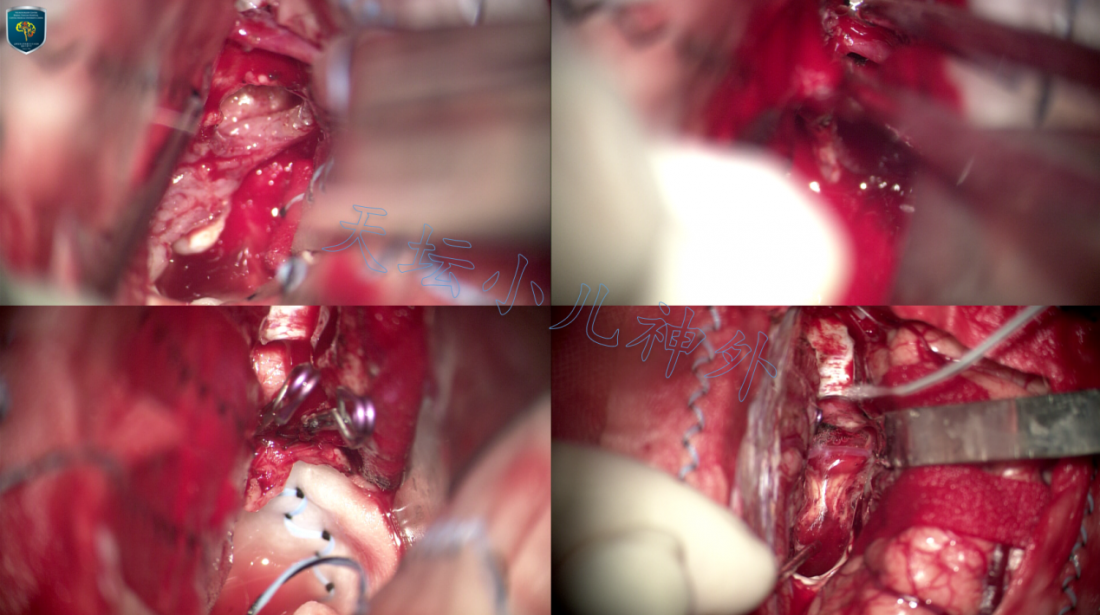

本例颅咽管瘤体积巨大,囊性主体突入第三脑室,第一间隙狭小,手术只能通过终板间隙(第四间隙)施行肿瘤切除。依据天坛小儿神外诊疗规范(附链接),先行Ommaya囊腔穿刺,囊液抽吸缓解梗阻性脑积水,待两周后瘤体缩小,瘤壁与下丘脑松解后再行手术,大大提高了手术安全性。

由于颅咽管瘤位于中线,我们的原则是:“中线肿瘤中线入路”,经前纵裂可视为天坛小儿神外切除颅咽管瘤的“黄金”入路。该入路沿脑组织自然间隙接近肿瘤,暴露广阔、无死角,重要结构均在肿瘤边缘,可在直视下妥善保护。

前纵裂入路需要特别关注的解剖结构是前交通动脉,磁共振T2矢状位可以清晰显示肿瘤与前交通动脉的位置关系,为通过哪一解剖间隙切除肿瘤提供依据。若手术涉及第四间隙,由于切除肿瘤需要在第三脑室操作,术后下丘脑反应明显重于单纯第一间隙操作。尽管理论上,前交通动脉平均长度可达12.7mm,有足够的活动度与延展性1,但本例宽度小于1.0cm,为向两侧牵拉额叶从而充分暴露终板间隙增加了难度。有日本学者认为可以主动牺牲前交通动脉换取足够的手术视野2,但前交通动脉发出多簇穿支动脉(下丘脑支、视交叉支、胼胝体下动脉),特别是胼胝体下动脉常为单干,损伤后可能导致穹隆、胼胝体膝部梗塞3。因此,不宜主动切断前交通动脉,我们主张在保护好前交通动脉的基础上,通过锐性松解蛛网膜,达到最佳暴露效果。

当然,任何经前纵裂手术都要做好前交通动脉破裂出血的预案。北京天坛医院小儿神经外科每年完成经前纵裂入路鞍区肿瘤切除术近200例,术中出现前交通动脉破裂出血的情况3-5例(约1-2%)。一旦术中破裂出血,术者要沉着冷静,吸引器准确指向破裂口,防止血液倒灌至深方造成急性脑膨出。无论电凝烧灼或动脉瘤夹夹闭,一定要确切止血,切记不要海绵压迫5,或采取肌肉粘附破裂口;一旦迟发出血,患儿剧烈头痛后瞬间昏迷,严重者危及生命,我们曾有类似教训,在此提醒同行切记!